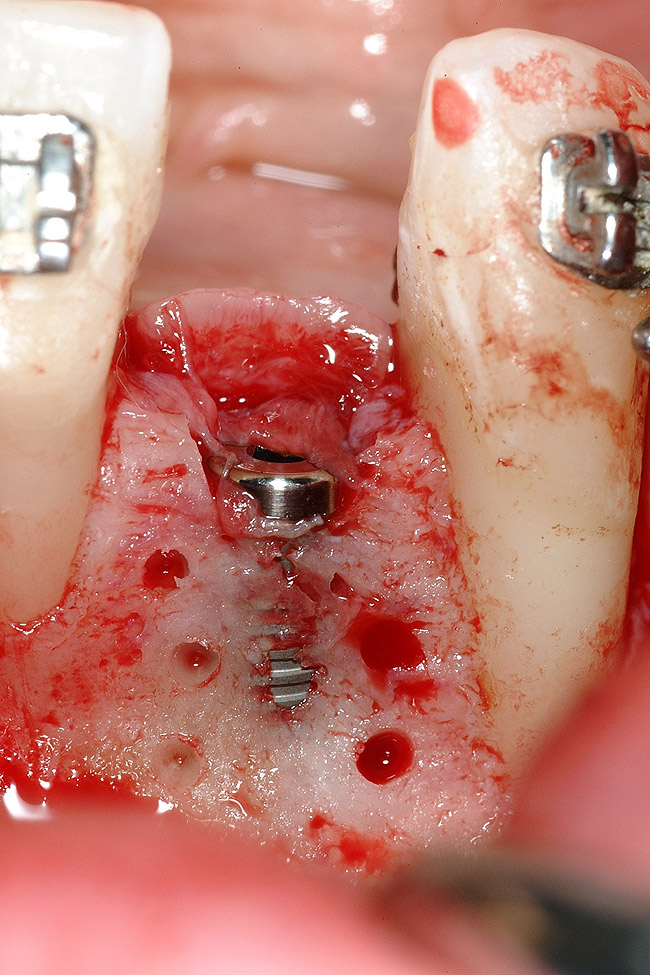

Figure 18  Implant placement with resulting facial dehiscence. Cortical perforations placed to promote angiogenesis.

Figure 18

Figure 19  Mineralized freeze-dried bone allograft hydrated with platelet-derived growth factor covering root dehiscences and implant dehiscence.

Figure 19